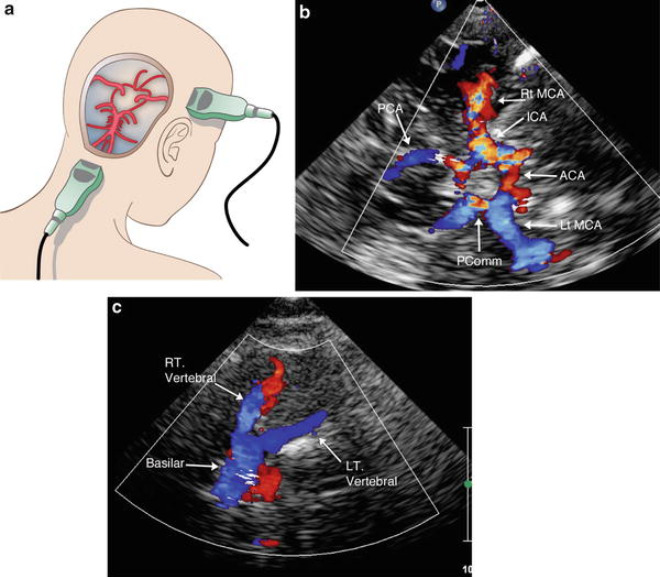

Trong siêu âm Doppler xuyên sọ, sóng âm thanh được gửi qua các mô trong hộp sọ. Những sóng âm thanh này phản xạ các tế bào máu di chuyển trong mạch máu, cho phép bác sĩ X-quang hoặc bác sĩ thần kinh giải thích tốc độ và hướng của chúng. Các sóng âm thanh được ghi lại và hiển thị trên màn hình máy tính.

- Đầu dò gửi sóng âm tần số cao qua não và thu nhận thông tin lưu lượng máu trở lại. Tín hiệu siêu âm được chuyển thành đồ thị hoặc hình ảnh màu hiển thị trên màn hình hiển thị.